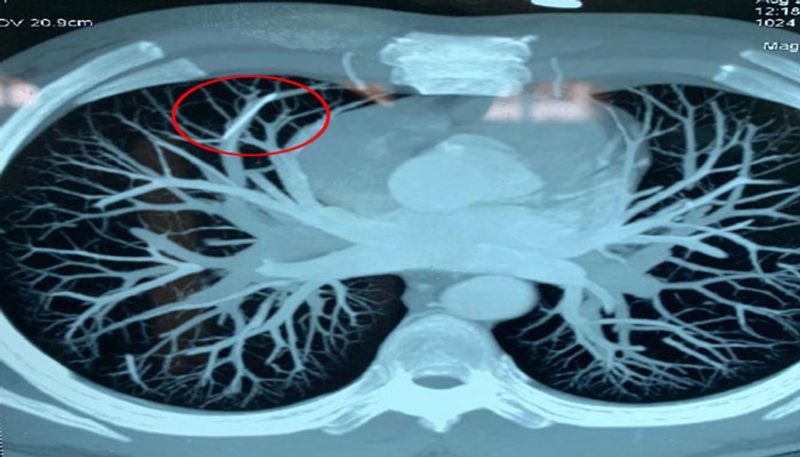

చివరకు ఈ నెల 18వ తేదీన సికింద్రాబాద్ గాంధీ దవాఖాన వైద్యులను సంప్రదించి కార్డియోథోరాసిక్ విభాగంలో పరీక్షలు చేయించుకోగా ఊపిరితిత్తిలో కాన్యులా ముక్క కనిపించింది.

వెంటనే కార్డియోథొరాసిక్ వైద్యులు, అనస్తీషియా స్పెషలిస్టులు రెండుగంటలపాటు శస్త్రచికిత్స నిర్వహించి సూది ముక్కను బయటకుతీశారు. ప్రస్తుతం కొవ్వాడయ్య కోలుకొంటున్నాడు. ఈ సందర్భంగా కొవ్వాడయ్య మీడియాతో మాట్లాడుతూ.. గాంధీ వైద్యులు తనకు ఆపరేషన్ చేసి మరో జన్మనిచ్చారని కృతజ్ఞతలు తెలిపారు. ప్రభుత్వ హాస్పిటల్ లో ఇంత బాగా చూసుకొనే డాక్టర్లు ఉండటం ప్రజల అదృష్టమని, ఇక్కడి వైద్యులందరికీ రుణపడి ఉంటానన్నారు.